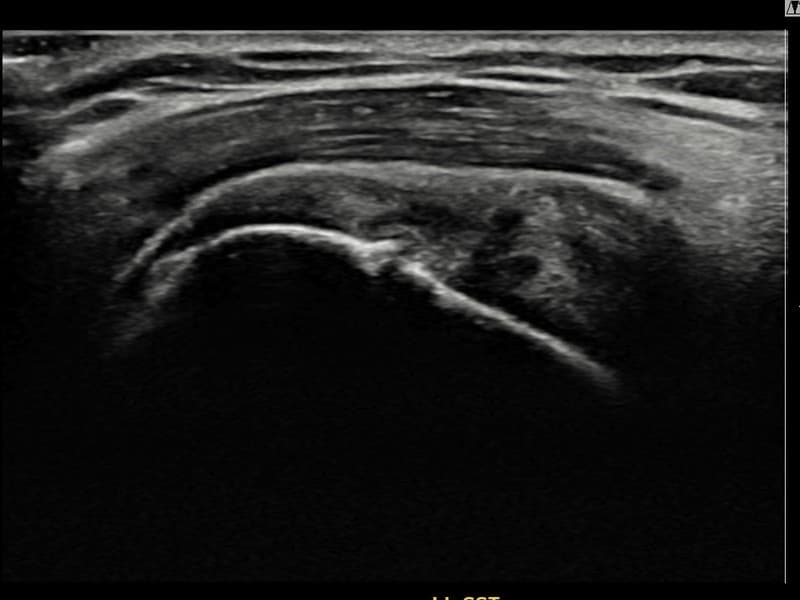

Before

시술 전 초음파 측정 결과 파열 크기는 8mm × 3mm (힘줄 두께의 약 30% 결손)로 확인되었습니다. 시술 전 초음파에서 좌측 극상근건 관절면측의 에코 소실과 힘줄 경계 불명확화가 확인되었습니다. 시술 후 초음파에서 관절면측 힘줄 경계가 선명해지고 에코 패턴이 정상으로 회복된 것이 관찰되었습니다.

40대 후반 여성 환자분으로, 테니스를 즐겨 하시다 왼쪽 어깨에 통증이 생겨 운동을 중단하셨습니다. 이후 일상적인 동작에서도 통증이 지속되어 내원하셨으며, 초음파 검사에서 좌측 극상근건 관절면측 부분파열이 확인되었습니다. 파열 범위가 비교적 초기 단계이나 방치 시 진행될 수 있어 조기에 초음파 유도 하 축소봉합술을 시행하였습니다. 시술은 20분 이내에 완료되었고 당일 귀가하셨으며, 보조기 착용 4주 후 단계적 운동 복귀 프로그램을 진행하였습니다. 시술 13주 후 추적 초음파에서 극상근건 관절면측 연속성이 완전히 회복된 것이 확인되어 테니스 복귀에 성공하셨습니다.